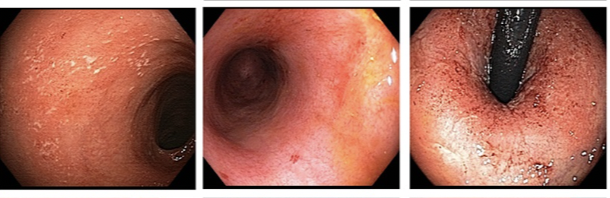

Mayo score?